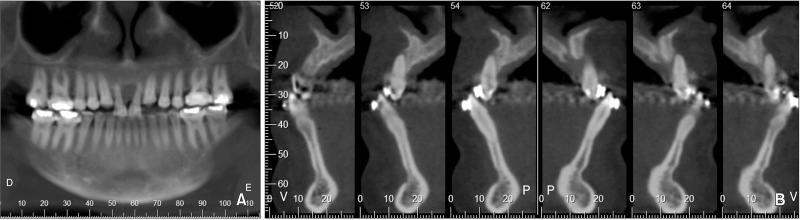

The aim of this clinical report is to describe the complex treatment of an adult Class III malocclusion patient who was disappointed with the outcome of a previous oral rehabilitation. Interdisciplinary treatment planning was performed with a primary indication for implant removal because of marginal bone loss and gingival recession, followed by orthodontic and surgical procedures to correct the esthetics and skeletal malocclusion. The comprehensive treatment approach included: (1) implant removal in the area of the central incisors; (2) combined orthodontic decompensation with mesial displacement and forced extrusion of the lateral incisors; (3) extraction of the lateral incisors and placement of new implants corresponding to the central incisors, which received provisional crowns; (4) orthognathic surgery for maxillary advancement to improve occlusal and facial relationships; and finally, (5) orthodontic refinement followed by definitive prosthetic rehabilitation of the maxillary central incisors and reshaping of the adjacent teeth. At the three-year follow-up, clinical and radiographic examinations showed successful replacement of the central incisors and improved skeletal and esthetic appearances. Moreover, a Class II molar relationship was obtained with an ideal overbite, overjet, and intercuspation. In conclusion, we report the successful esthetic anterior rehabilitation of a complex case in which interdisciplinary treatment planning improved facial harmony, provided gingival architecture with sufficient width and thickness, and improved smile esthetics, resulting in enhanced patient comfort and satisfaction. This clinical case report might be useful to improve facial esthetics and occlusion in patients with dentoalveolar and skeletal defects.

本临床报告旨在描述一名成年III类错牙合患者的复杂治疗过程,该患者对先前口腔修复的结果不满意。由于边缘骨丢失和牙龈退缩,进行了跨学科治疗计划,主要指征是移除种植体,随后进行正畸和外科手术以纠正美观和骨骼错牙合问题。综合治疗方法包括:(1) 移除中切牙区域的种植体;(2) 联合正畸代偿,使侧切牙向近中移位并强行萌出;(3) 拔除侧切牙并在对应中切牙位置植入新的种植体,新种植体安装临时冠;(4) 进行正颌手术使上颌前徙,以改善咬合和面部关系;最后,(5) 正畸精细调整,随后对上颌中切牙进行最终的修复治疗并对相邻牙齿进行塑形。在三年随访时,临床和影像学检查显示中切牙成功替换,骨骼和美观外观均得到改善。此外,获得了II类磨牙关系,覆牙合、覆盖和牙尖交错关系理想。总之,我们报告了一例复杂病例的成功美学上前牙修复,其中跨学科治疗计划改善了面部和谐,为牙龈结构提供了足够的宽度和厚度,改善了微笑美学,提高了患者的舒适度和满意度。本临床病例报告可能有助于改善牙列和骨骼缺陷患者的面部美学和咬合情况。